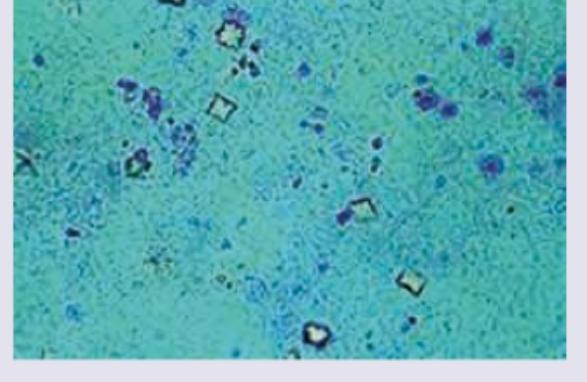

An unconscious patient was brought to the casualty. ABG reveals metabolic acidosis with hypocalcemia. The urine specimen from this patient is shown below. Identify the substance:

Explanation: ***Ethylene glycol*** - The image shows **calcium oxalate crystals** (both monohydrate, "dumbbell" shapes, and dihydrate, "envelope" shapes), classical findings in **ethylene glycol poisoning**. - Ethylene glycol is metabolized into **oxalic acid**, which precipitates with calcium, leading to **hypocalcemia** and metabolic acidosis due to accumulating organic acids. *Methyl alcohol* - Methyl alcohol poisoning is characterized by metabolites like **formic acid**, causing severe **metabolic acidosis** and visual disturbances, but does not typically lead to calcium oxalate crystalluria. - While it causes profound acidosis, the diagnostic urine crystals seen in the image are not associated with methyl alcohol intoxication. *Formaldehyde* - Formaldehyde poisoning is generally due to ingestion or inhalation, leading to immediate toxicity, often with severe gastrointestinal and respiratory symptoms. - It does not typically metabolize into substances that form **calcium oxalate crystals** in the urine or cause hypocalcemia in this manner. *Paraldehyde* - Paraldehyde is an older sedative/hypnotic that can cause **metabolic acidosis** due to its metabolism into acetic acid, especially in large doses. - However, it does not lead to the formation of **calcium oxalate crystals** in the urine or associated hypocalcemia as seen in the image.